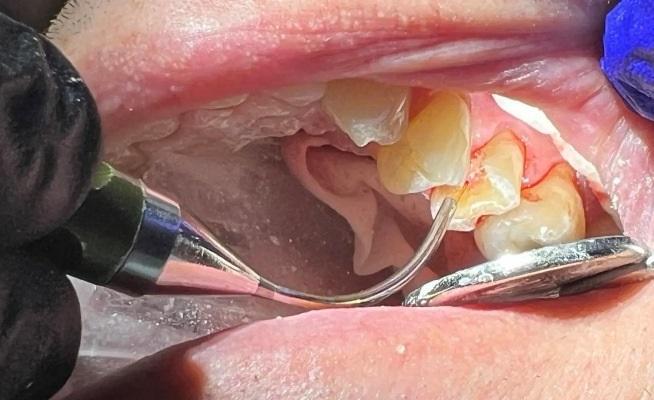

Лазерное лечение пульпы потенциально позволяет избежать эндодонтического лечения

Обработка пульпы Nd:YAG-лазером для устранения любых бактерий, которые могли привести к инфицированию пульпы и вызвать необходимость эндодонтического лечения.